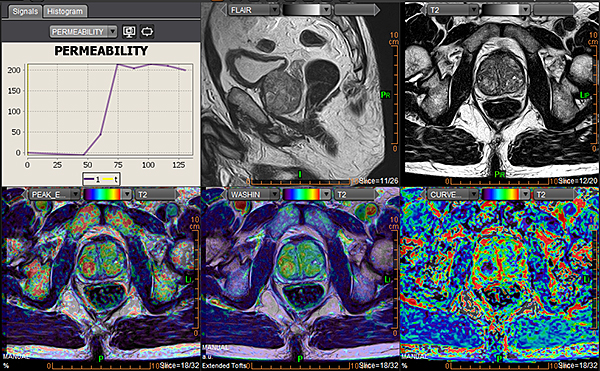

Magnētiskās rezonanses (MR) izmeklējums prostatai tiek veikts, lai detalizēti izvērtētu prostatas struktūru un patoloģiskas izmaiņas.

PI-RADS ir sistēma, ko radiologi izmanto, lai novērtētu prostatas MR attēlos redzamās izmaiņas un noteiktu, cik lielā mērā tās varētu būt saistītas ar prostatas vēzi.

PI-RADS vērtējums tiek izteikts ar ciparu no 1 līdz 5:

• PI-RADS 1–2 nozīmē, ka ļaundabīga procesa iespējamība ir ļoti zema,

• PI-RADS 3 – neskaidra atrade,

• PI-RADS 4–5 – paaugstināta iespējamība, ka atradums varētu būt vēzis.

Svarīgi saprast, ka PI-RADS vērtējums pats par sevi nav diagnoze – tas tikai norāda, cik liels ir ļaundabīga procesa risks. Galīgo apstiprinājumu sniedz biopsija vai histoloģiska analīze.